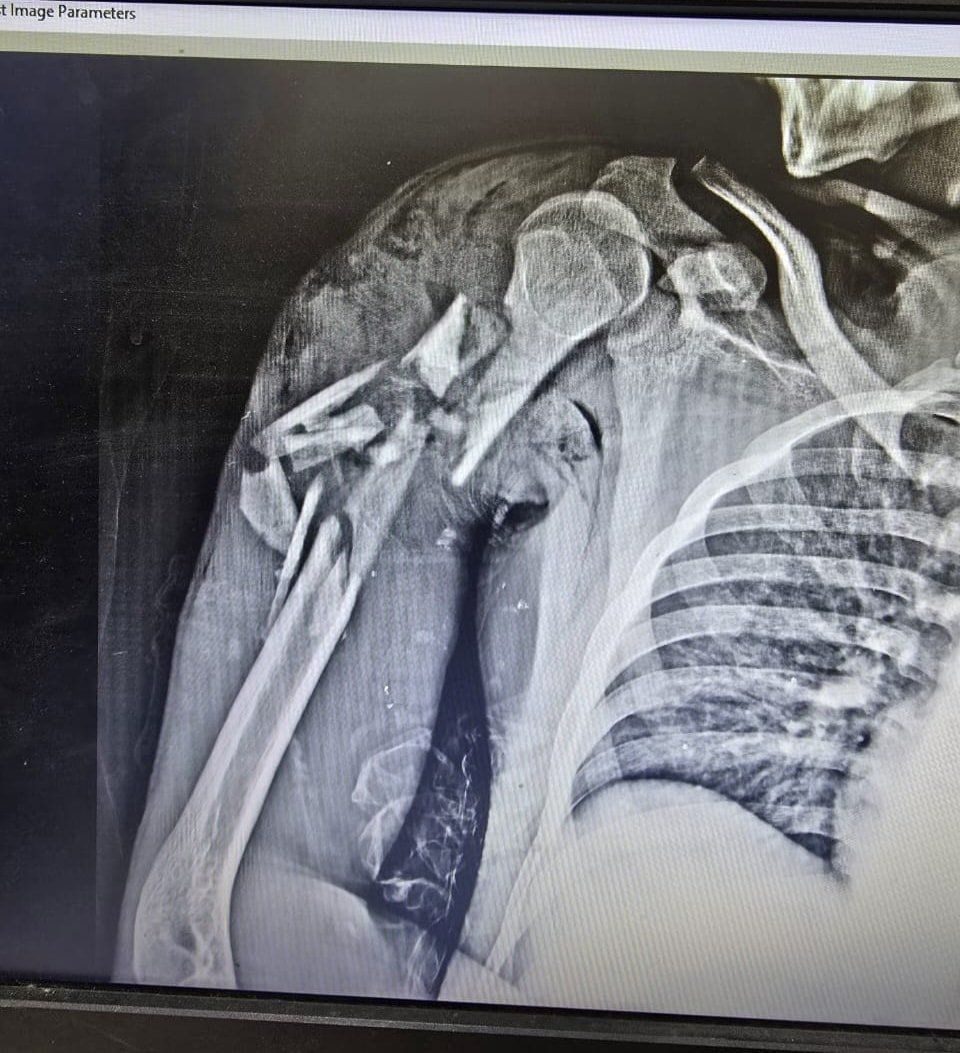

الإثنين، 06 أكتوبر 2025 01:50 منجح فريق جراحي بمستشفى قها التخصصي، التابعة لأمانة المستشفيات المتخصصة بوزارة الصحة، بمحافظة القليوبية، في إنقاذ حياة شاب في الـ20 من عمره، اصطدم به قطار، وكاد الحادث أن يودي بحياته، وتسبب في إصابته بكسر متفتت مفتوح مع فقد جزء من العظام بالعضد الأيمن مع قطع بالعضلات، وكسر متفتت مفتوح مع فقد جزء من العظام بالساق الأيمن مع قطع بالعضلات، وتهتك بالقدم اليمنى وقطع بالأوتار والعضلات، مع كسر بعظام القدم.

وتابعت المستشفى، أنه تم تجهيز المريض ولياقته من قسم التخدير وتحضيره وتجهيز الدم والبلازما اللازمة للحالة، حيث استقر التشخيص علي كسر متفتت مفتوح مع فقد جزء من العظام بالعضد الأيمن مع قطع بالعضلات، وكسر متفتت مفتوح مع فقد جزء من العظام بالساق الأيمن مع قطع بالعضلات، وتهتك بالقدم اليمنى وقطع بالأوتار والعضلات، مع كسر بعظام القدم.

أثناء الجراحة

الأشعة الخاصة بالمريض